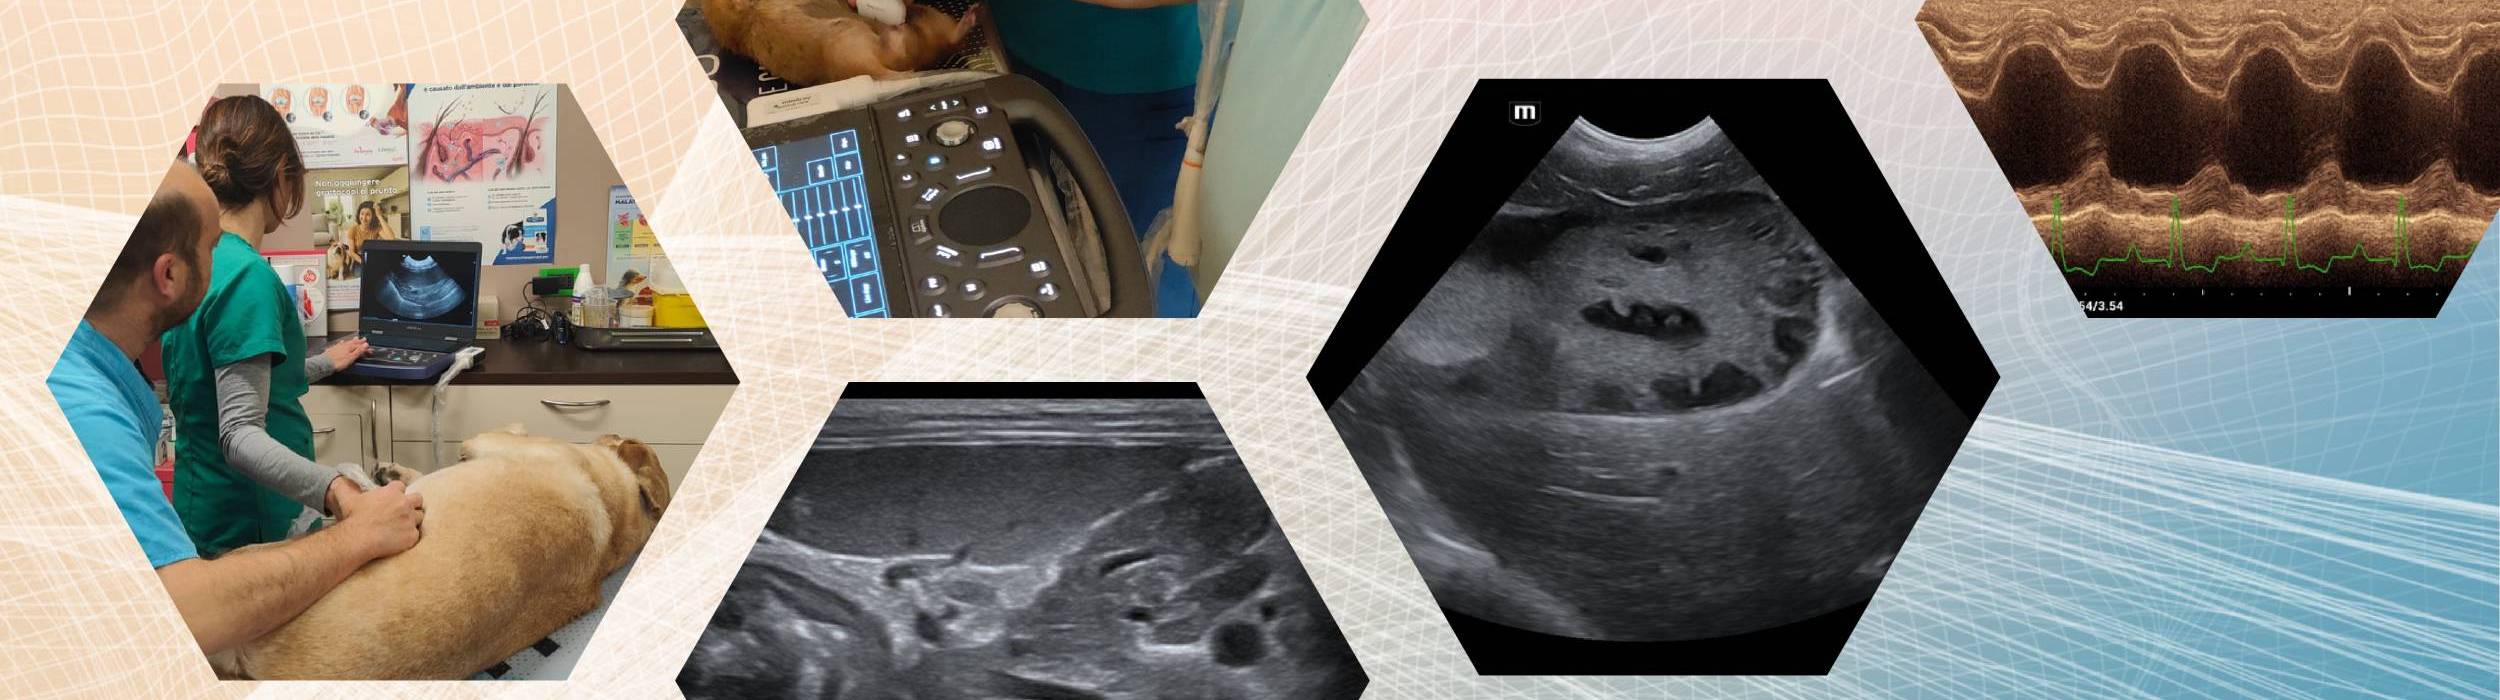

Il corso intermedio di ecografia addominale veterinaria è un percorso avanzato dedicato allo studio dell’addome patologico nel cane e nel gatto.

L’approccio è fortemente orientato alla semeiotica ecografica, al riconoscimento dei pattern patologici e alla loro corretta interpretazione clinica, con integrazione costante tra teoria, casi clinici ed esercitazioni pratiche.

Il corso è rivolto a veterinari che possiedono già conoscenze di anatomia ecografica normale e desiderano approfondire l’interpretazione delle alterazioni patologiche.